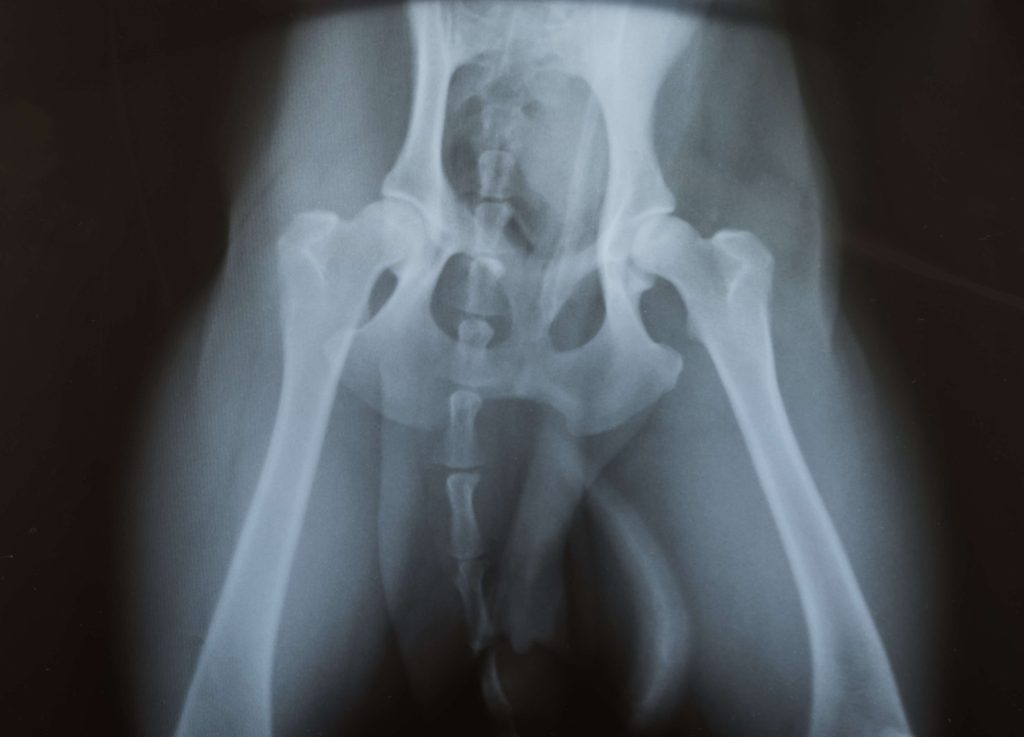

X-ray

New England Veterinary Services has a cutting edge X-ray system that provides instant images of premium quality to help diagnose pathology in your pet. It is mobile to allow field x-ray as well so it’s not limited to just the…

Orthopaedic Surgery

NEVS offers a number of orthopaedic surgical procedures for bone fractures and joint problems We use the latest plating technology including locking plates. Services include – fracture repair, amputation, hip toggles, treatment of luxating patella (trochleoplasty, tibial tuberosity transposition), cruciate…